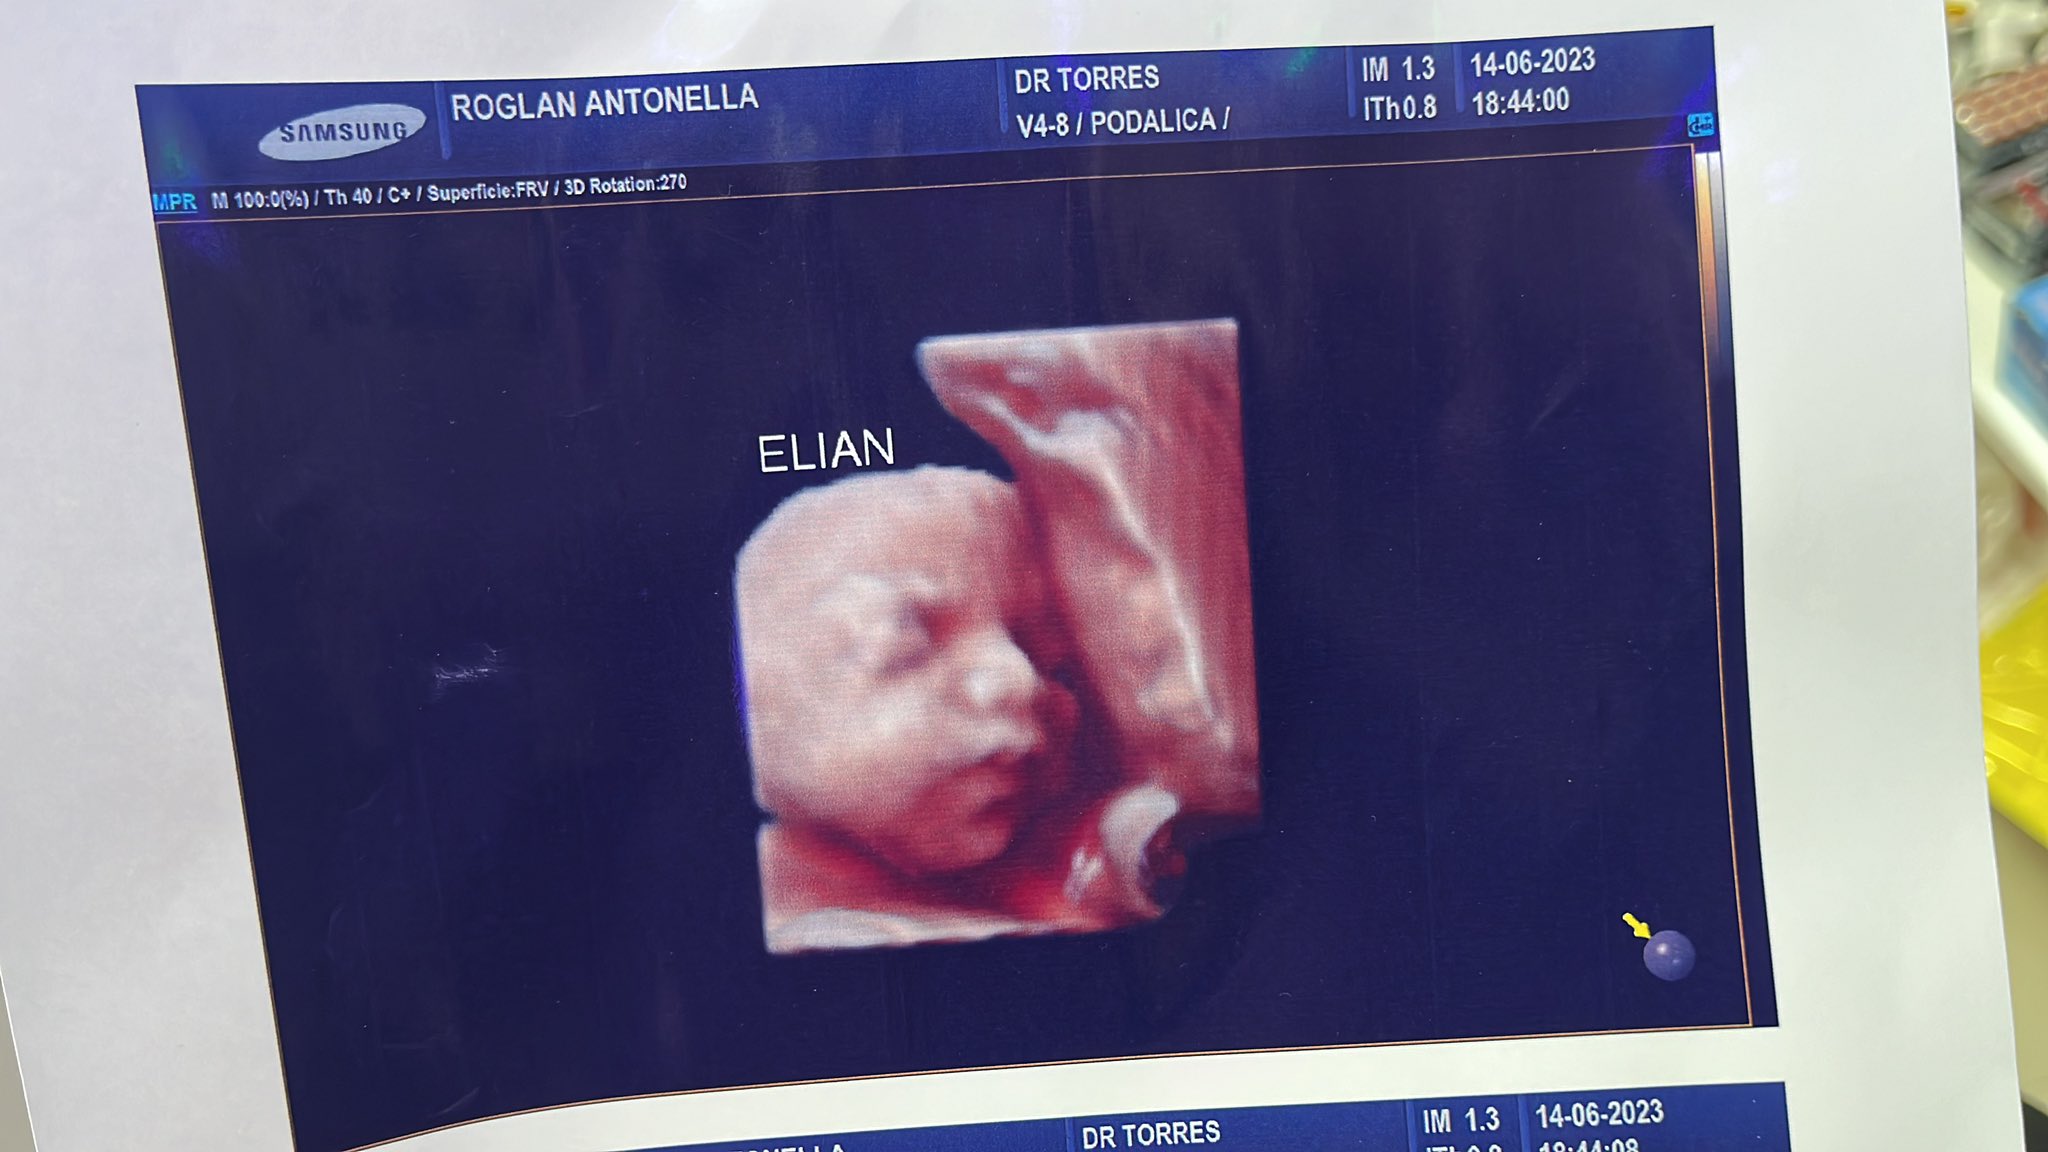

Una mujer de Argentina llamada Antonella Roglan, vio el video en TikTok e inmediatamente notó que la imagen de ese bebé era similar a la ecografía que le dieron de su hijo. Algo que comprobó al comparar las imágenes en cuestión.

“Por ahora somos 3 mamás a las que una clínica ESTAFÓ con una foto de un bebé que no es el nuestro, está de más decir que encima que cobran carísimo”, indicó la mujer en su cuenta de Twitter donde denunció lo ocurrido con EcoDiagnóstico.

“Uno se va ilusionado por ver a su bebé y tener un lindo recuerdo. Estamos en busca de más mamás con el mismo bebé”, dijo la mujer que mostró las ecografías donde efectivamente la imagen de los fetos son las mismas, aunque de diferentes mamás.

En las repuestas del tuit varias mujeres han posteado sus ecografías hechas en dicha clínica y en donde varias de ellas comparten al mismo bebé, ya que las ecografías son idénticas hasta en la posición de los fetos. Y al parecer el lugar ha hecho lo mismo desde hace años.